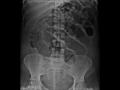

Figura 1 - Radiografia simples de abdome, demonstrando  ar na cavidade peritoneal, caracterizada por área radiolucente no hemiabdomen direito (seta). Adjacente à mesma pode ser identificada  imagem linear radiodensa, correspondendo ao ligamento falciforme (seta),  que só foi visibilizado devido à interface com o ar livre na cavidade peritoneal.

Figura 2 - Radiografia simples de abdome realizada em decúbito dorsal com os raios horizontais, demonstrando ar livre visibilizado entre a parede intestinal e o fígado (seta).

Figura 3 - Radiografia simples de abdome realizada em decúbito dorsal com os raios verticais evidencia aumento da quantidade de ar livre na cavidade peritoneal em relação aos exames anteriores (seta). Identificado o sinal de Riegler – visibilização da parede da alça devido à interface entre o ar dentro e fora da alça intestinal (setas).

Figura 4 - Radiografia simples de abdome realizada em decúbito dorsal com raios horizontais, demonstrando o aumento de ar livre visibilizado entre a parede intestinal e o fígado (setas longas). O sinal de Riegler também é identificado (seta curta).